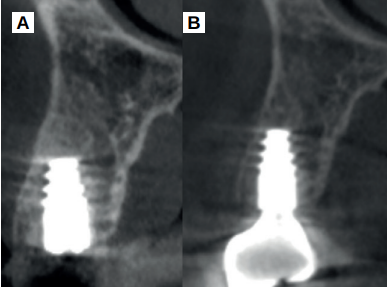

Caso clínico: se presenta el caso clínico de una mujer de 61 años, que acudió a consulta presentando dolor intenso en la zona del segundo premolar superior derecho (1.5). Se realizó la exodoncia del 1.5, usándose como diente donante para realizar una preservación del alveolo tras la extracción. Cuatro meses tras el procedimiento, se colocó un implante y se tomó una biopsia para realizar un análisis histomorfométrico. Un año tras la carga del implante se observaron buenos resultados clínicos y radiográficos.

Clinical case: a 61-year-old woman is presented, who came to private dental clinic presenting intense pain in the area of an upper bicuspid of the first quadrant (1.5). Exodontia of the 1.5 was performed, using it as a donor tooth to obtain the biomaterial to preserve its alveolus. After 4 months re-entry was performed and an implant was placed, harvesting a bone biopsy for histomorphometric analysis. One year post-loading, good clinical and radiographic results were shown.